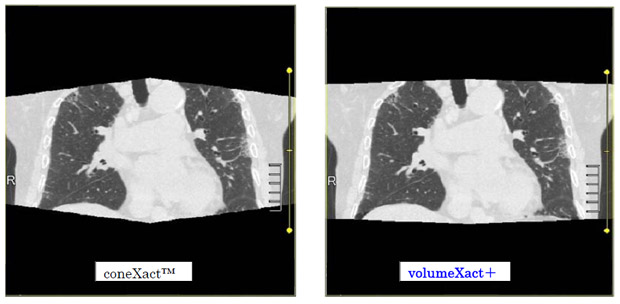

3. Volume Scan & Wide Volume Scan

新開発の画像再構成VolumeXact+(ボリュームイグザクトプラス)を搭載し,Volume Scan時の画像表示領域を拡張。Wide Volume Scanにおいても連続性と均一性に優れたデータを描出する。従来のヘリカルスキャンに比べ被ばく,解像度で優れるArea Detector CTならではのVolume Scanの可能性をさらに広げる。